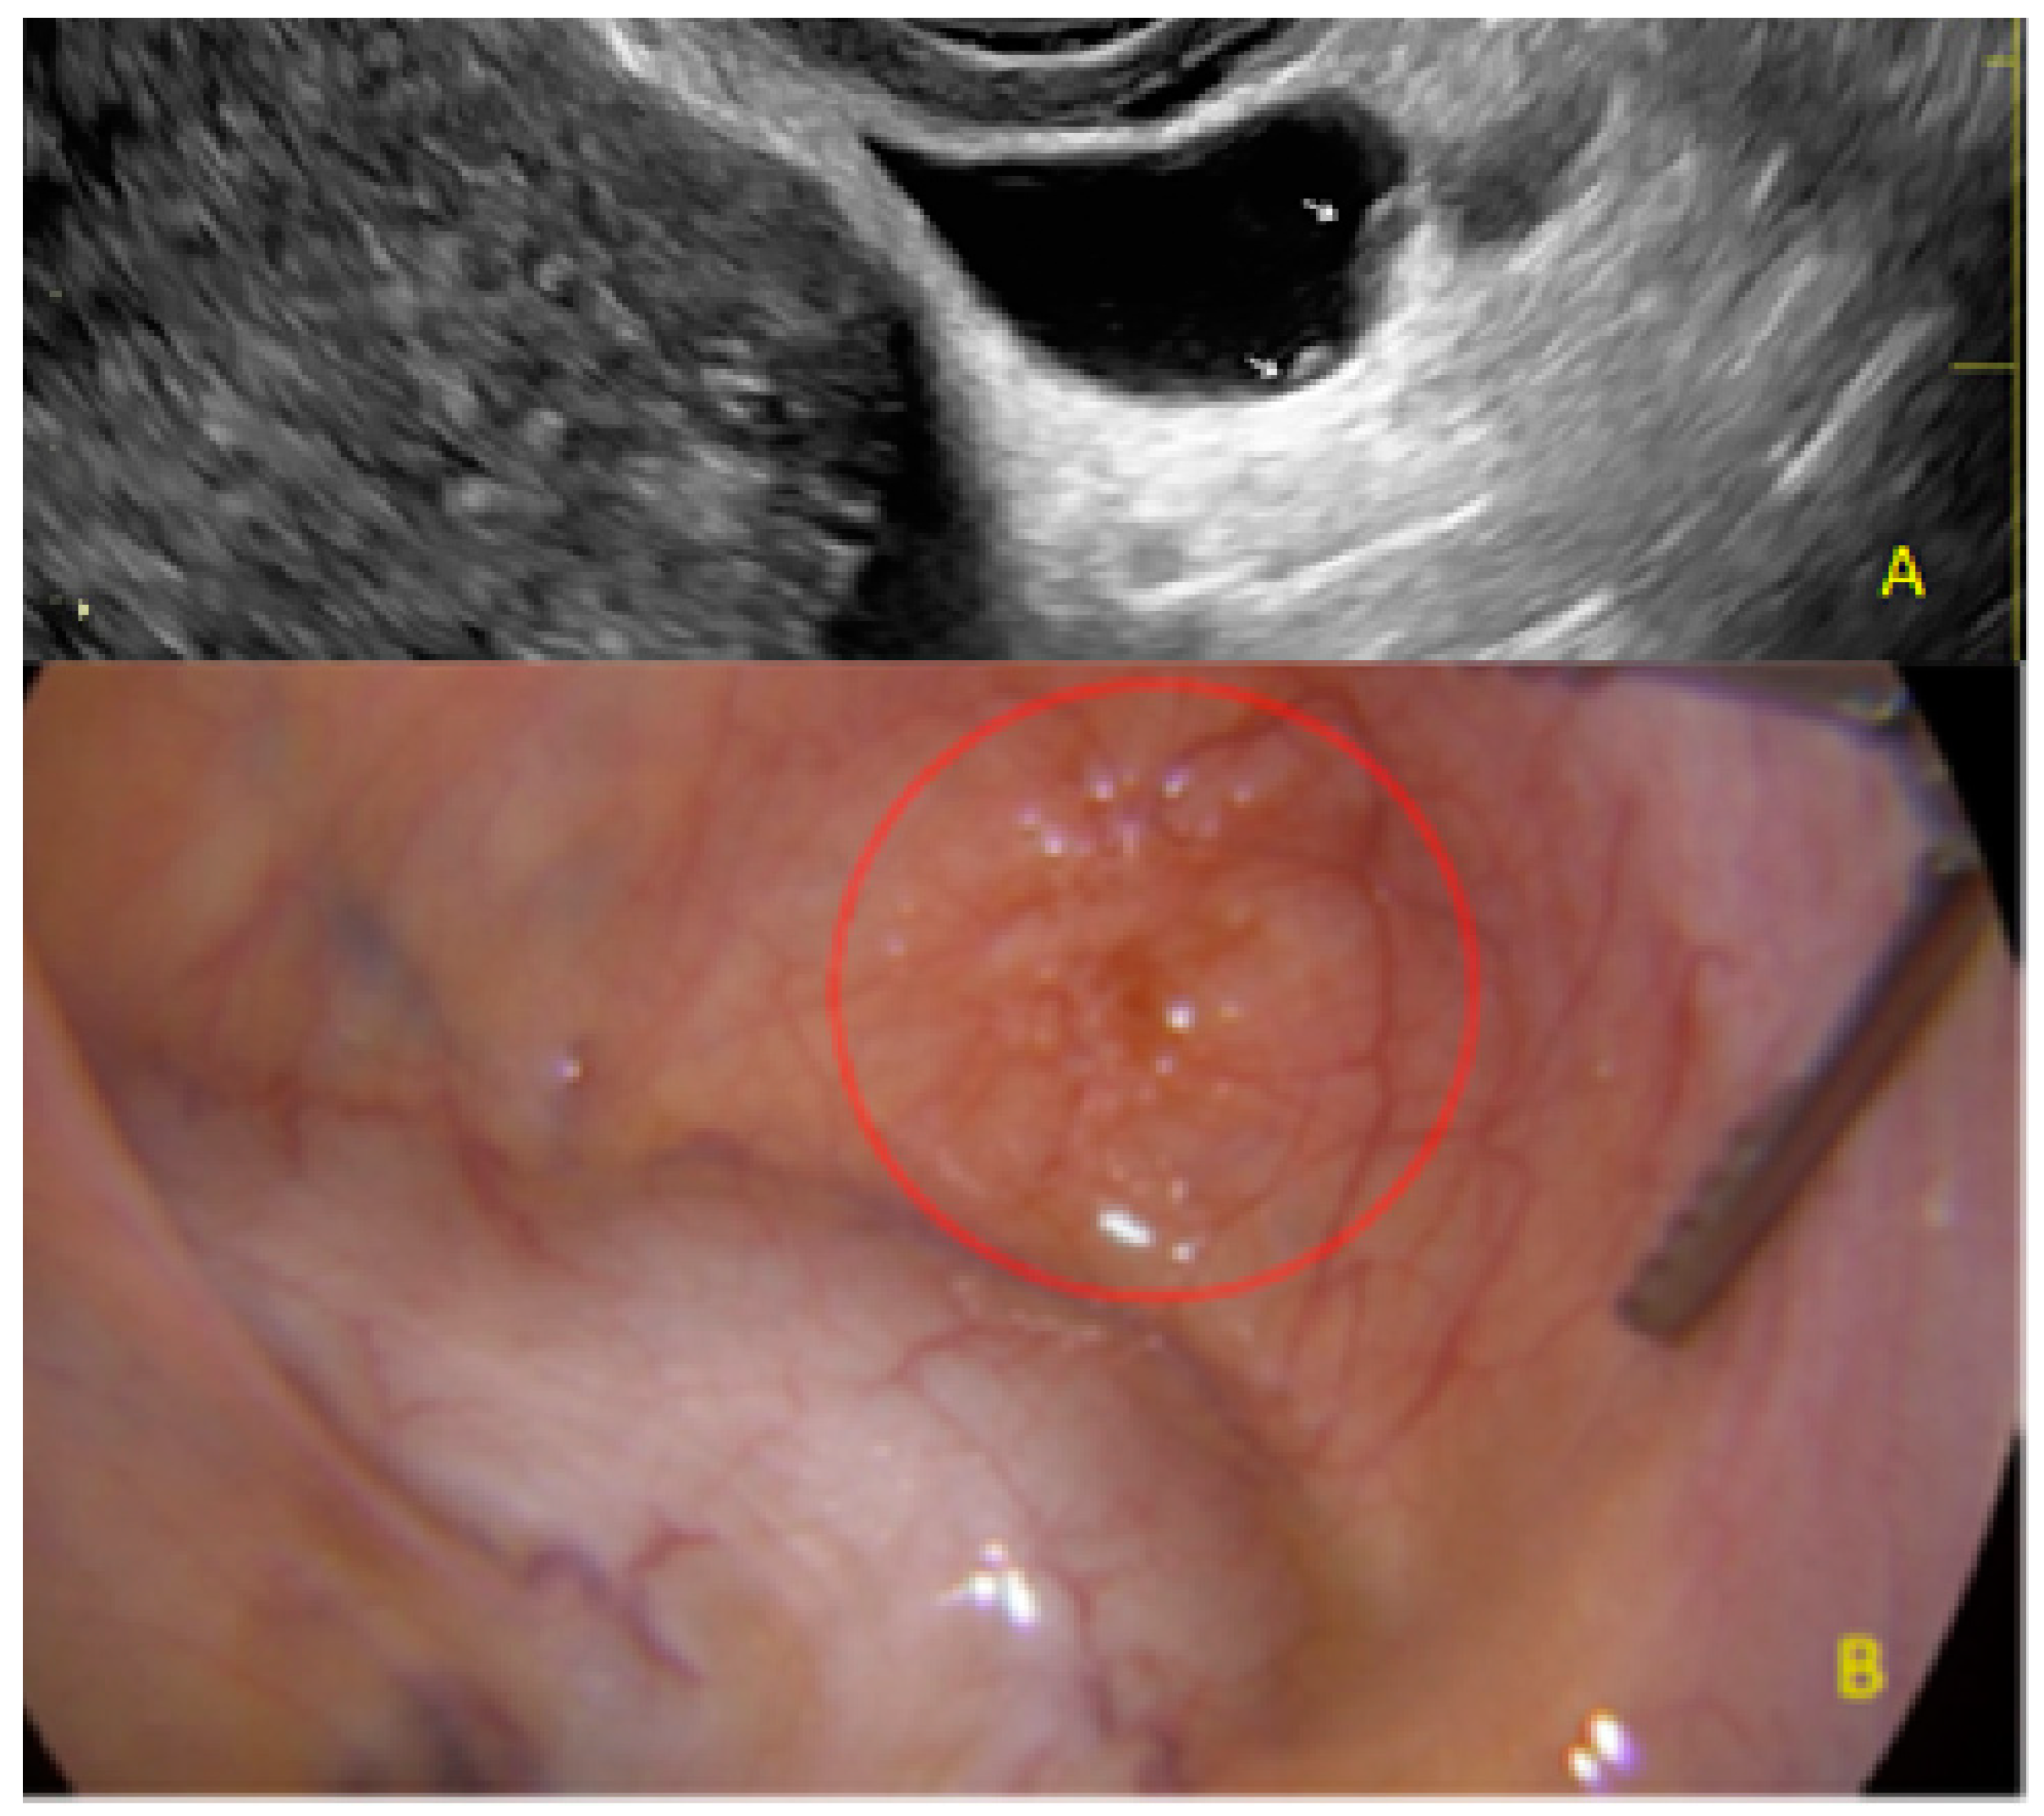

- The presence of hyperechoic foci (we called this a “pearl”).

3.1. Cystic Solitary Lesion